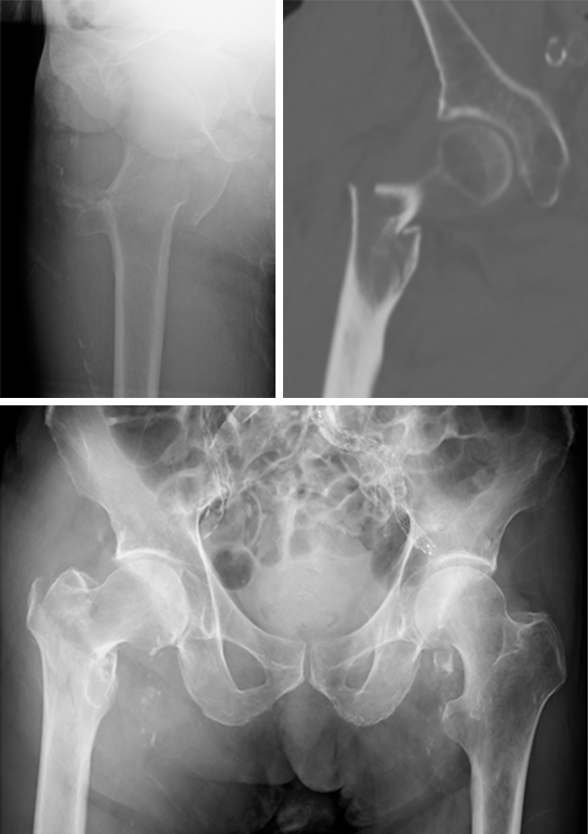

It is widely reported in the literature in Japan that there are many missed unstable femoral trochanteric fracture cases diagnosed only by x-ray, yet CT scans can clearly reveal the unstable fracture pattern.

A 77-year-old man suffered a right femoral trochanteric fracture (Figs 5-8). This case can be diagnosed as AO31-A1. However, the CT shows the detachment of the lesser trochanter (AO31-A2). Precise information of dangerous fracture patterns in advance might simplify the imaging of intraoperative reduction maneuvers and the use of the implants.

In this case, the fracture lines are located in the area of the intended nail insertion point. The 3-D reconstruction images distinctly show that the hollow reamer prevented the fracture fragments from being pushed apart when introducing the hollow reamer close to the fracture line.